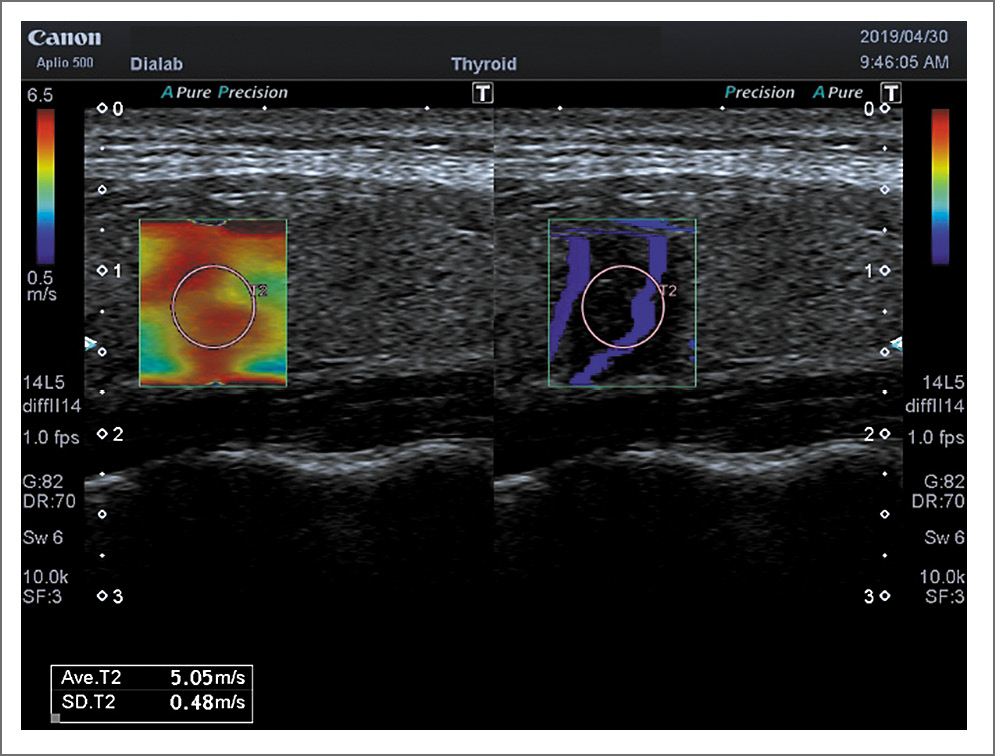

Рис. 5. ПР. Shear Wave – 77,6 кПа

Наши данные относительно показателей жесткости неизменной паренхимы ЩЖ в контрольной группе практически совпадают с данными литературы. Так, по данным А.Н. Катрич и соавт. [28], значение модуля Юнга составило 13,75 кПа, В.В. Митькова и соавт. [29] – 12,5 кПа, по данным В.С. Паршина и соавт. [30] – 15,60 кПа. Значение модуля Юнга в злокачественных образованиях ЩЖ по данным А.Н. Катрич и соавт. [28] составило 48,78 кПа (13,67–60,0 кПа), по результатам наших исследований – несколько выше – 67,0±1,9 кПА (135,0; 34,0 кПА); рис. 7, 8.

Рис. 7. ПР. Shear Wave – 5,05 м/с